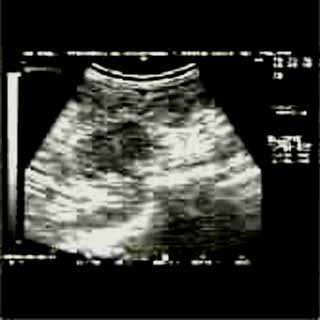

Oι τελευταίες 4 απεικονίσεις έγιναν με ειδικό για μαστό ηχοβολέα linear, εναλλασσομένης συχνότητος 7,5-10ΜΗΖ.